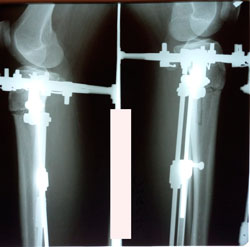

до круток

image-02-02-21-03-13-1.jpg

image-02-02-21-03-13.jpg